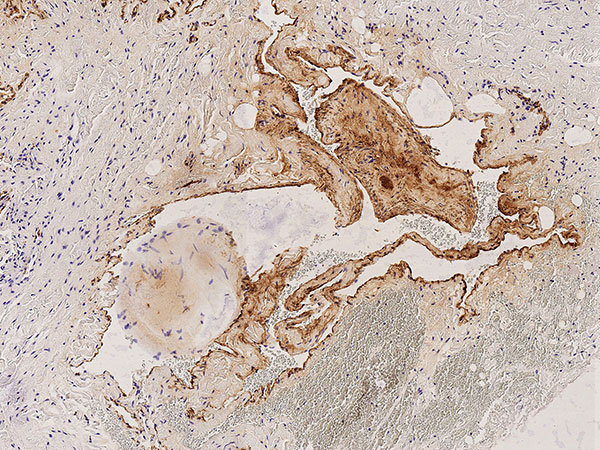

Histopathology, CD31 staining, 110× magnification: Strong staining (dark brown-stained cells) of the entire border of the irregular, vascular dysplastic cavities with the vascular endothelium-specific marker CD31 clearly indicates a vascular malformation. Only a very thin vessel wall is detectable beneath the vascular endothelium.

Histopathology, D2-40 stain, 95× magnification: The vascular endothelial lining of the multiple irregular vascular spaces does not stain with podoplanin (D2-40). Thus, they are not lymphatic vascular endothelia. In conjunction with the wall structure and the shape of the lesion, this is another clear indication of a venous malformation (not a lymphatic malformation).